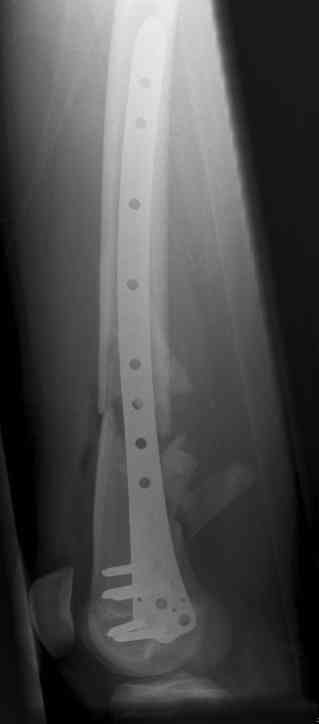

16 yr old boy, high energy motorcycle trauma trauma in July 2005 with:

- hip dislocation + acetabular fracture L

- distal femoral fracture L

- tibial shaft fracture L

- metatarsal fractures L

july 05: LISS femur, LCP plate tibia, double recon. plate post. acetabulum

feb 07: retrograde nail + bone graft + BMP

nov 07: persistant non-union distal femur; other fractures healed